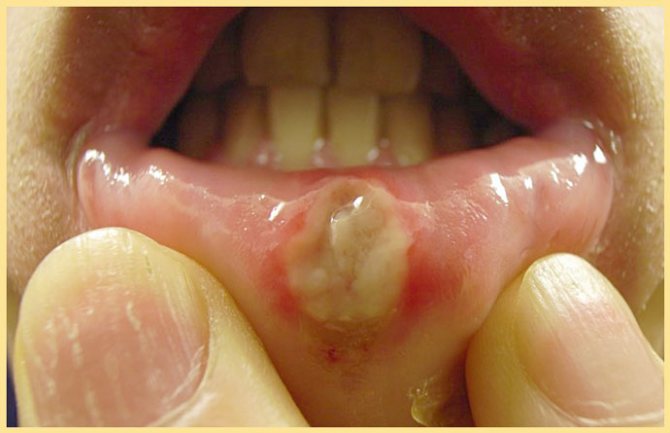

Афтозный стоматит обычно появляется на подвижных частях рта, таких, как язык или внутренняя поверхность губ и щек, и у основы десен. Язвы выглядят поначалу как маленькие овальные или круглые красноватые опухоли, которые обычно появляются в течение дня. Разорванные язвы покрыты тонкой белой или желтой мембраной и окружены по краю красным кругом. В основном, язвы заживают в течение двух недель, не образуя шрамов. Жар возникает редко и язвы редко связаны с другими заболеваниями. Обычно у человека появляется одна или несколько язв за один раз.

- Афтозный стоматит — возникает в результате ослабления защитных функций организма, острого недостатка витаминов группы С и В, а также попадания в ротовую полость бактерий. При афтозном стоматите в ротовой полости (на внутренней стороне губ и щёк, а также на небе и зыке) появляются болезненные язвочки серовато-беловатого цвета. Такие язвочки доставляют большой дискомфорт при приёме пищи так, как болезненно реагируют на солёные и кислые продукты.

- Афтозный стоматит. При такой патологии язвочки возникают на губах, внутренней стороне щек, языке, вдобавок поражая небо. Правильно спланировав лечебный курс, можно устранить проявления патологии за 10-14 дней. Когда ранки полностью заживут, вместо них появятся мелкие рубцы. Причина такого заболевания может крыться даже в обычном нервном расстройстве, сильном стрессе или гормональном сбое.